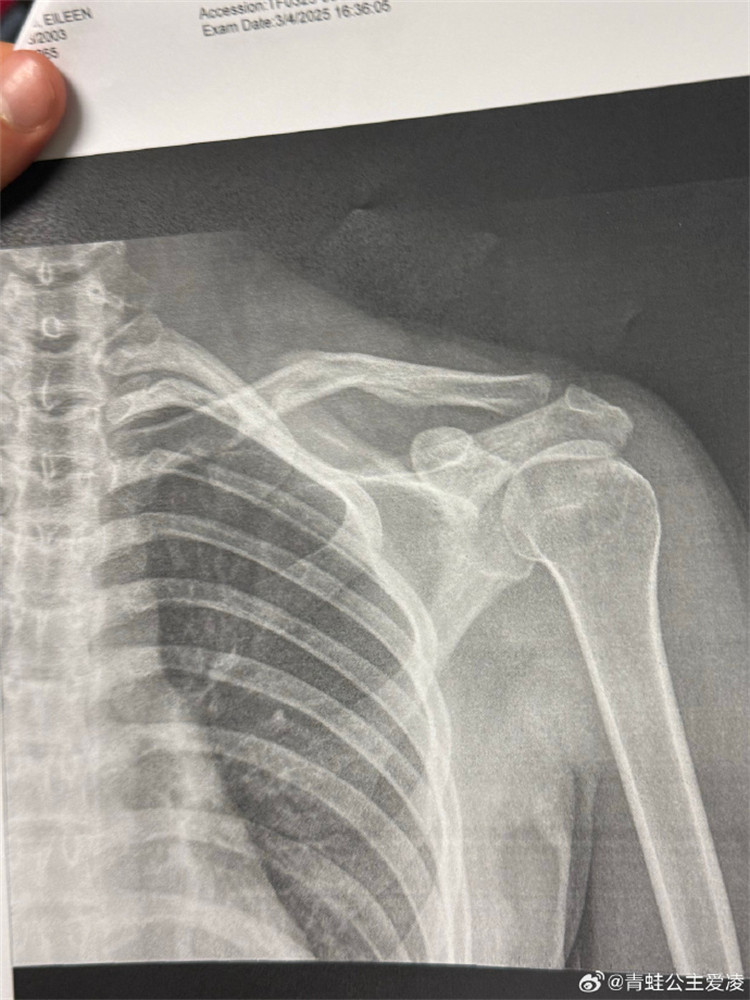

今年3月9日,谷愛凌在社交媒體曬出肩部骨折的X光照片,並配上一個(gè)心碎的表情,隨後相關(guān)話題登上熱搜。